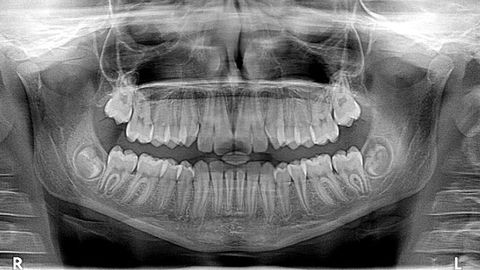

La Consejería de Sanidad podrá poner a disposición de todos los pacientes que lo reclamen los historiales clínicos de iDental después de que el juzgado le haya dado acceso a  para que ponga en marcha su digitalización con el propósito de dar oportuna información a los afectados. Después de que se decretara el cierre de la clínica de Gijón en el mes de junio, la Audiencia Nacional asumió la investigación de la estafa en todo el territorio nacional en julio, señalando que la documentación y los historiales clínicos de los pacientes quedaran bajo custodia de los departamentos de Sanidad de las distintas comunidades autónomas. En Asturias se ha guardado en el depósito del Huca 298 cajas precintadas con esa documentación. El 10 de septiembre se recibió un auto de la Audiencia Nacional con instrucciones para que, previo desprecintado judicial, se procediera a «la ordenación, escaneado y entrega de las historias clínicas de los pacientes de iDental» de manera que el proceso fuera asumido por personal del SESPA y «habilitándose un procedimiento para entregar en soporte digital las historias clínicas a los pacientes que lo soliciten y sin necesidad de solicitud expresa».

En agosto, la Policía Judicial registró junto a inspectores de Sanidad la clínica de Idental en Gijón incautándose de 297 cajas con las historias clínicas de los pacientes. Después de la clausura de la sede de la clínica, las demandas de pacientes ante los servicios de consumo se dispararon. En septiembre constaban ante la administración asturiana 1019 de las cuales, la gran mayoría, alrededor del 80% tienen incluida la financiación del tratamiento a través de un crédito vinculado.